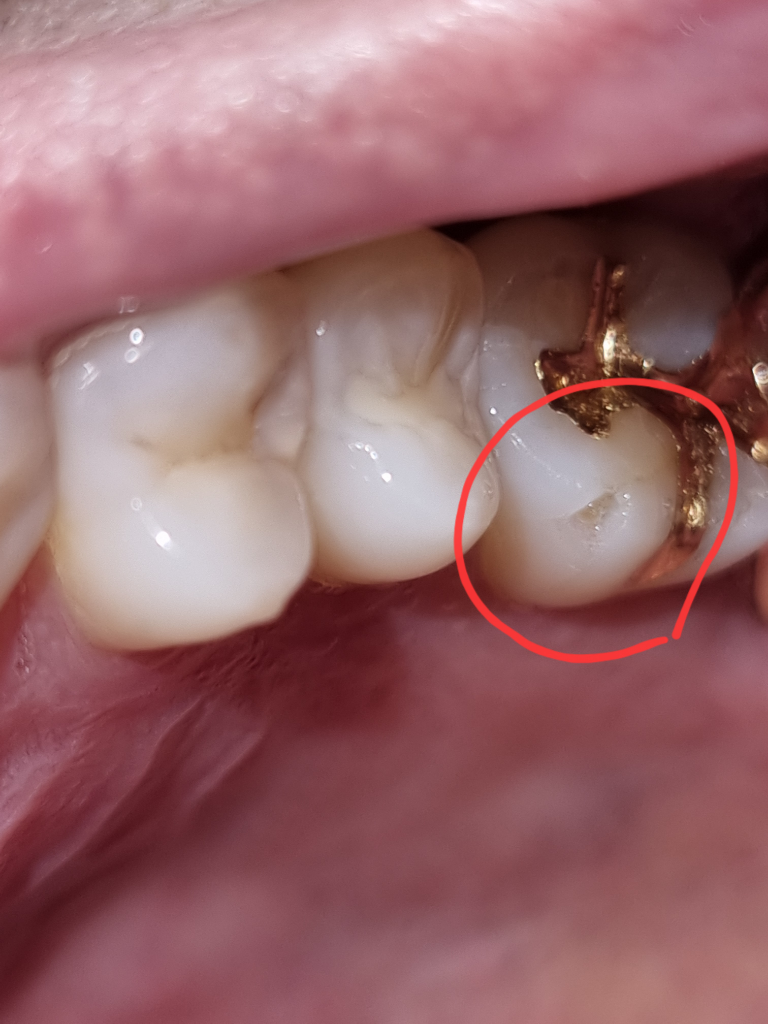

치아 일부분 끝부분만 떨어져 나간 상태입니다, 떨어져 나가 약간 파인 것으로 보이니 이 파인 부분만 떼우고 전체적으로 씌우는

크라운은 하지 않아도 될 것으로 보입니다.

치과 방문 후 검사를 받아보셔야 합니다. 파절된 부위가 생각보다 크고 파절되고 남아 있는 치질에 금이 가 있는 것이 사진으로도 보입니다. 정확한 진단을 받아봐야 하고 금이 어느정도 파급되었는지에 따라 치료 과정이 달라질 것으로 보입니다. 통증이나 불편감이 없더라도 빠른 시일 내에 치과 방문 후 검진을 받아보시길 바랍니다.

저정도 크기면 사실 간단하게 떼우셔도 되지만, 기존에 치료를 받으신치아라 약간 걱정이 됩니다. 치과에 가셔서 전체적으로 검진을 받으신후 치아가 문제가 없다면 떼우는 치료를 하시고 증상이 있다면 크라운 또는 신경치료를 하셔야될수도 잇습니다.

일부분만 깨진 상태로 금이 가있는 것이 아니라면 깨진 부위만 레진으로 치료하시면 됩니다.

사진으로 봤을경우에는 보철물 주변으로 금이 가고 이로 인해서 치아가 파절된것으로 보입니다.